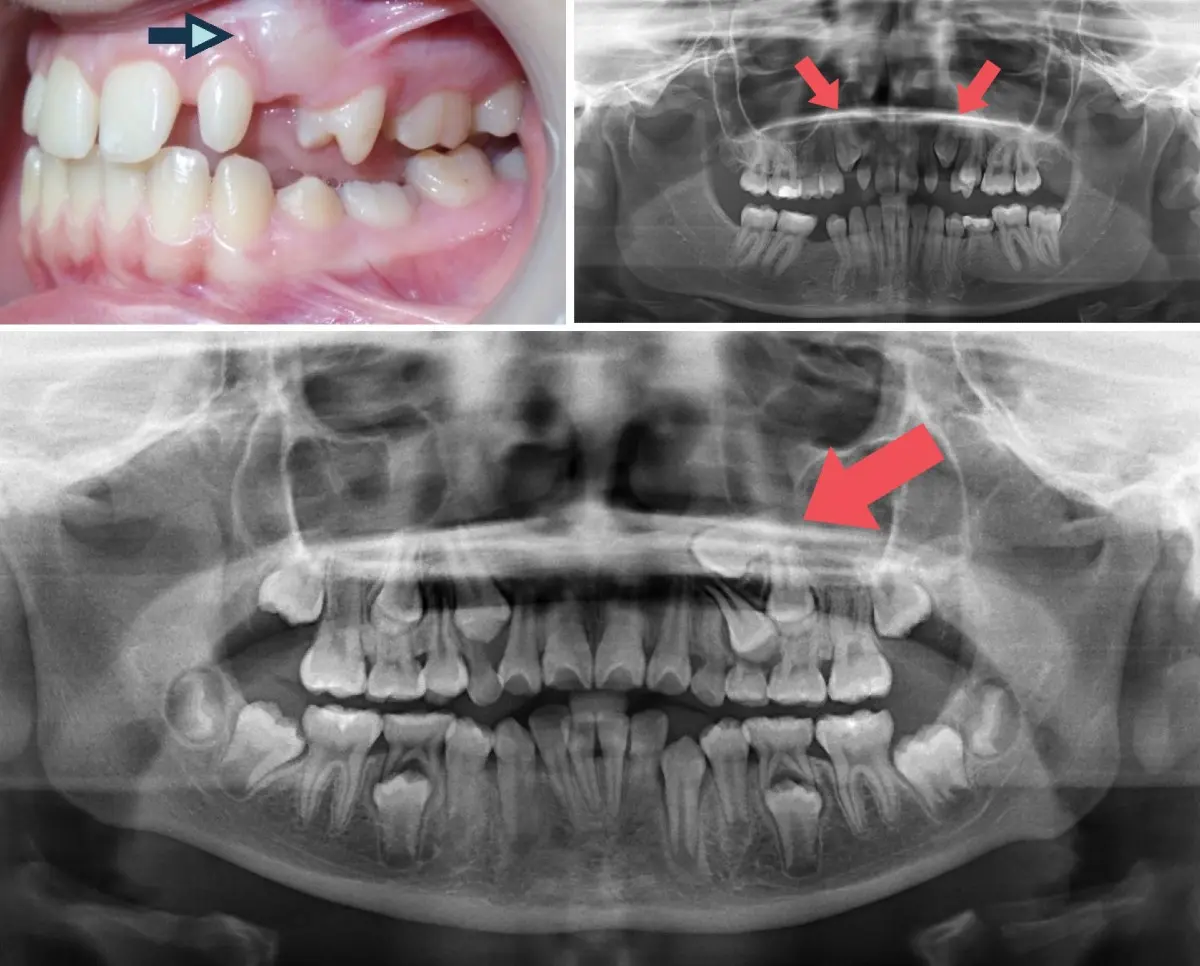

Braces to fix Impacted Canines McKee Dental Associates Braces For Impacted Teeth In some cases, though, patients may require oral surgery to help remove some of the gum tissue in order to allow more of the tooth to be exposed. Braces can align impacted teeth by applying gentle pressure over time. Diagnosis is based on clinical examination coupled with imaging, especially cone beam ct (cbct) scans. This means, instead of growing in. Braces For Impacted Teeth.

Impacted Teeth Mount Elizabeth Orthodontic Clinic Braces For Impacted Teeth For many patients, allowing adequate space for the tooth to erupt on its own will be enough. Braces can align impacted teeth by applying gentle pressure over time. Mandibular third molars are the most frequently impacted teeth, followed by maxillary third molars, maxillary canines, mandibular premolars, and maxillary incisors. Braces use brackets and wires to bring teeth into alignment. If. Braces For Impacted Teeth.

Impacted Teeth Mount Elizabeth Orthodontic Clinic Braces For Impacted Teeth Diagnosis is based on clinical examination coupled with imaging, especially cone beam ct (cbct) scans. Braces can align impacted teeth by applying gentle pressure over time. Braces can be used to help reposition the other teeth to make room for the tooth that is impacted. This helps guide teeth into the proper position, allowing. Mandibular third molars are the most. Braces For Impacted Teeth.